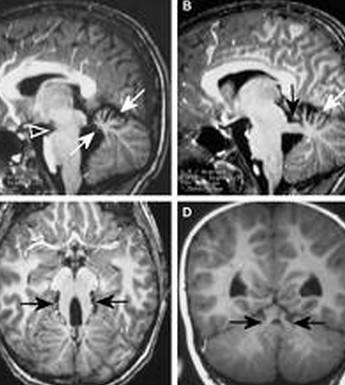

Parallel ventricles

Radial or pallisading gyri in sagittal plane

Colpocephaly

Longhorn or Viking helmit frontal horns

High riding 3rd vent

“Keyhole” temporal horns

Vascular anomalies: “wandering ACAs”

All 3 commissures are absent.

Cingulate gyrus (black arrows) “mirrors” the development of the corpus callosum.

Enlarged HC connects fornices, not cerebral hemispheres

Type I Communicating Cyst

Cyst communicates with the third ventricle.

Type II Complex

Noncommunicating Cyst(s) Cysts demonstrate differing signal characteristics than CSF.